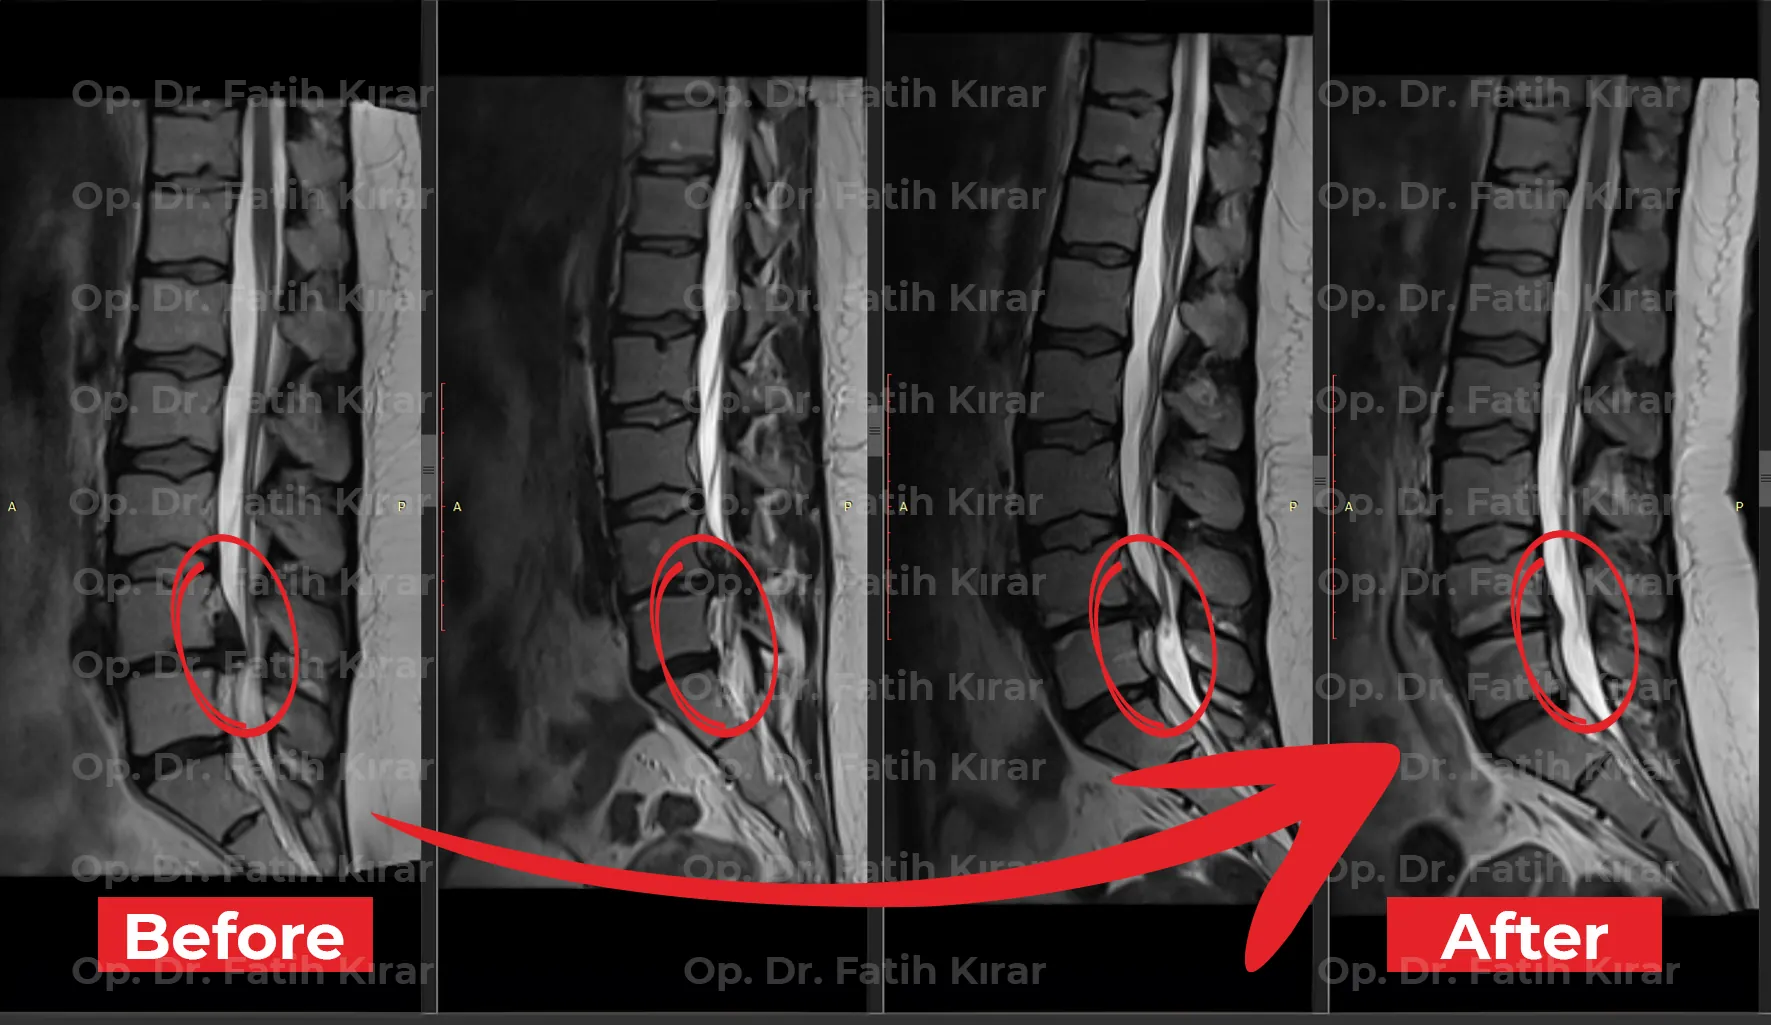

Gelişmiş fıtık tedavi sonuçlarımızdan gerçek önce ve sonra görüntüleri